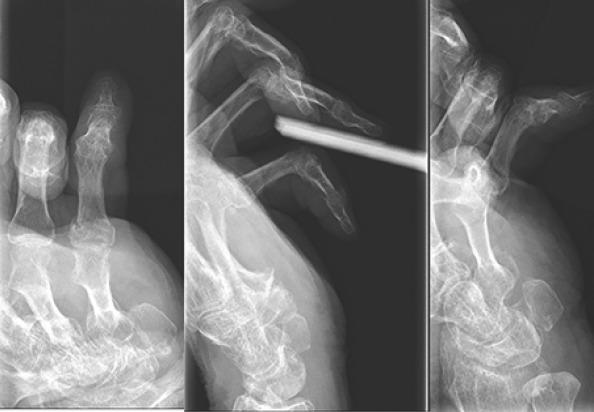

The patient is an 80-year-old right-hand dominant retired male with bilateral hand contractures and palmar fibromatosis. His medical history is notable for Type II diabetes mellitus and metastatic thyroid cancer. The patient underwent Xiaflex injection of the left small finger and returned 4 days later for planned release. An appreciable release of the contracture was noted; however, there was a concern for plastic deformation of the proximal phalanx as a result of the manipulation. X-rays confirmed the fracture and apex volar angulation at the base of the proximal phalanx. The fracture appeared amenable to non-operative treatment. The patient has been followed closely and has had no pain or tenderness at the fracture site and minimal swelling. X-rays at 1 week and 1 month showed maintained alignment and signs of consolidation at the fracture site. The patient is currently 4-month post-fracture, and no further intervention has been pursued.